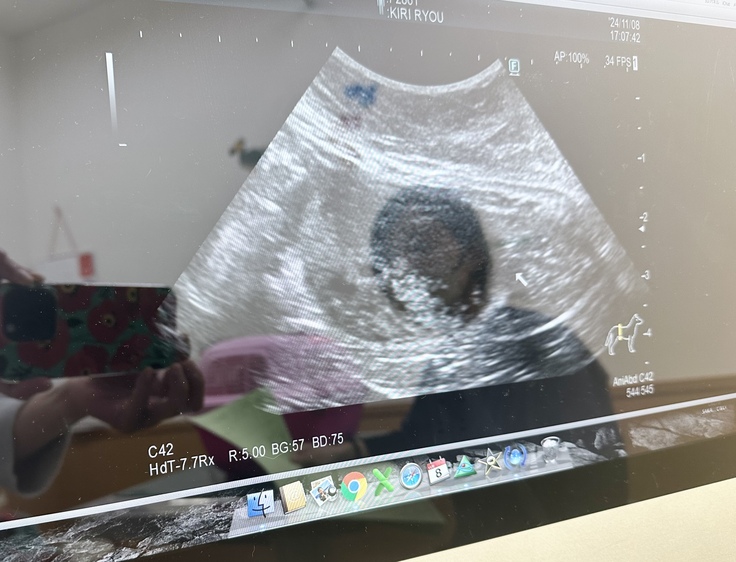

【今日の椋ちゃん】

ボロボロの猫小屋で生活してた猫家族。

膀胱結石による急性腎不全で生死を彷徨った

椋(りょう)ちゃん。

状態を観察しないといけないため、シェルターではなく私の自宅で療養中です。

治療食を食べていますが、すっきりしませんね〜😰

またまた膀胱結石が再発してしまいました💦

これからの季節、飲水量が減るので注意が必要ですね。

普段食べているストルバイトケア(テイスト)に加えてストルバイトケア(スターター)が追加になりました✨